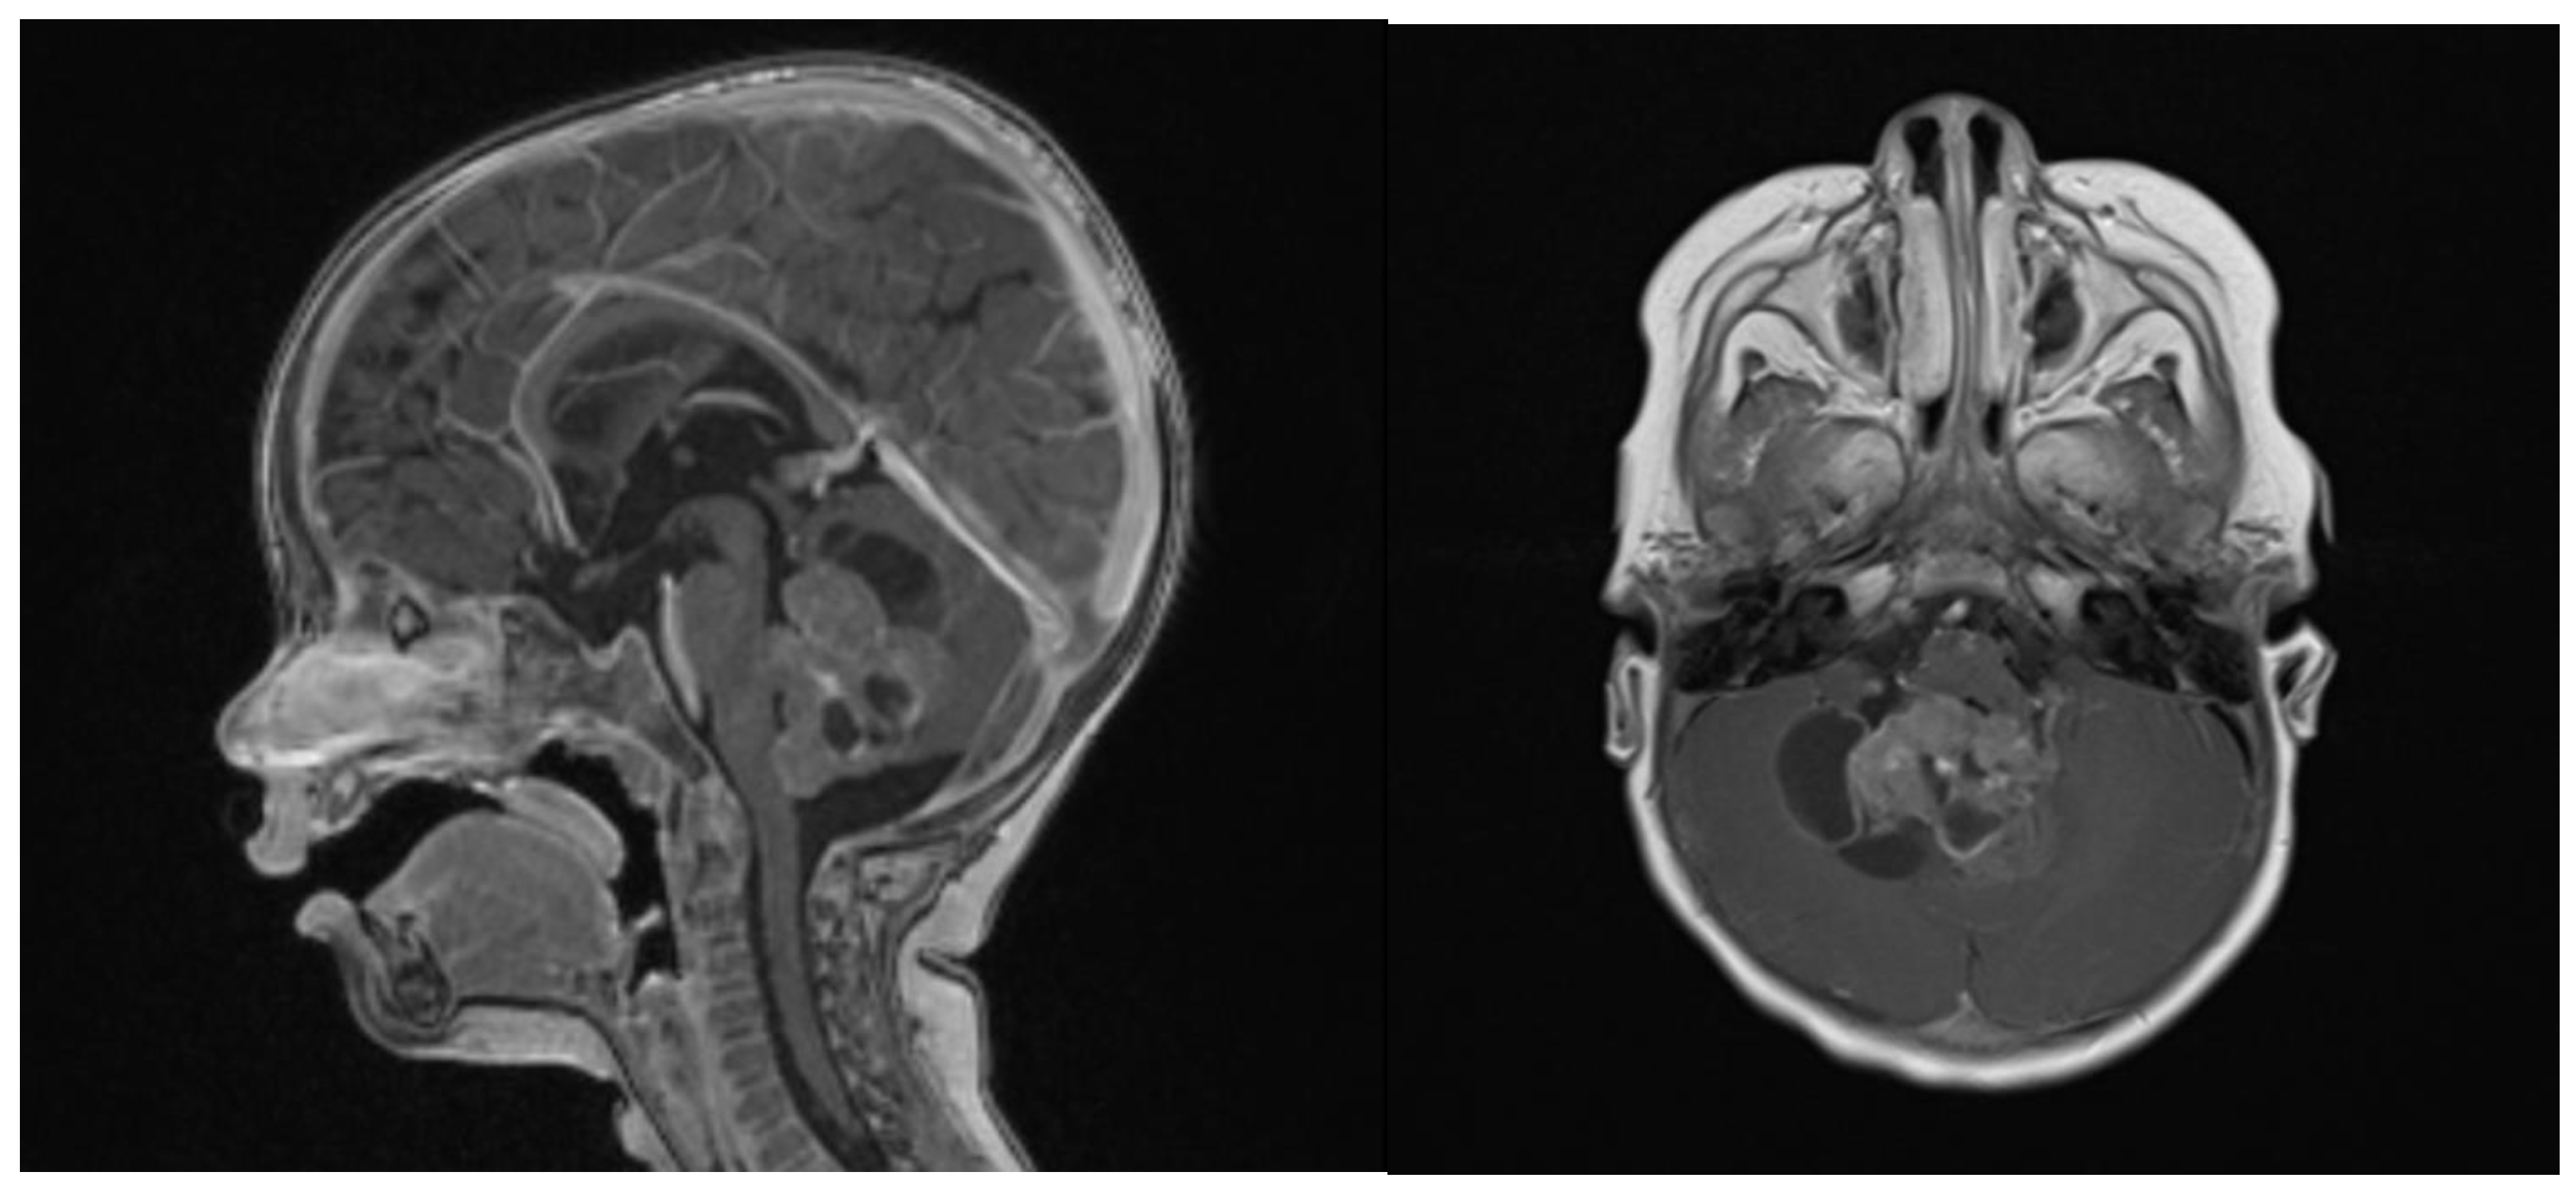

Clinical examination did not show any anterior fontanel bulging nor trismus. Whole brain and spine magnetic resonance imaging (MRI) was performed, showing a heterogeneous cystic-hemorrhagic lesion, partially calcified, in the posterior fossa, Measuring 46 × 34 × 49 mm and obstructing the IV ventricle and right Luschka foramen (Figure 2).

Figure 2.

Sagittal and axial gadolinium T1 MR sequence showing the exophytic mass occluding CSF diversion at the IV ventricle, compressing the brainstem and adjacent right cerebellar hemisphere.